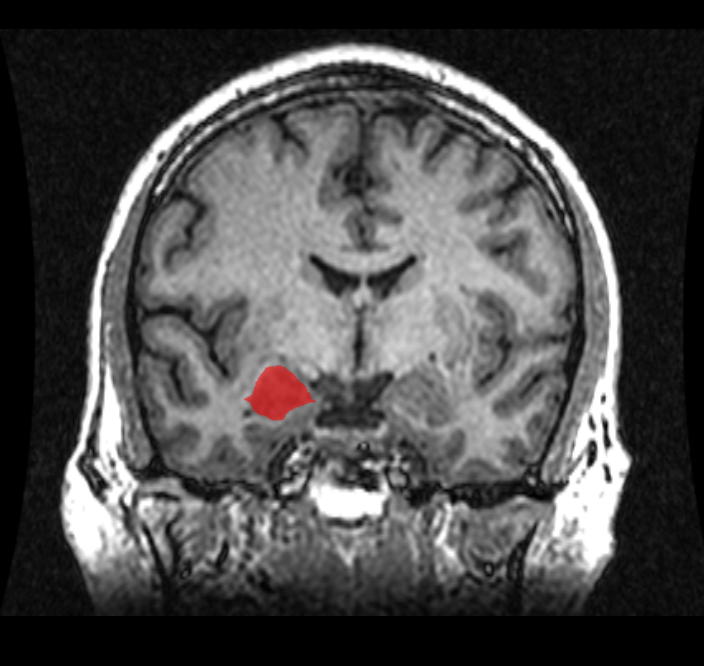

What does it mean, then, that the results in Ruch’s study suggest liberals are more likely to appreciate nonsense humor, while conservatives strongly prefer incongruity resolution? Evidence for one possible explanation comes indirectly from an MRI study that looked at differences in brain volume between liberals and conservatives.6 Conducted by a team that included Academy Award-winning actor Colin Firth (because apparently a relaxing thing to do in your downtime as a highly successful actor is participate in peer-reviewed academic research), their results showed that liberalism was associated with an increased volume of the anterior cingulate cortex.

Interestingly, the anterior cingulate is most often seen as a sort of conflict mediator in the brain, one that works to help monitor uncertainties and navigate contradictions rather than avoid them. In fact, the anterior cingulate region of the brain shows the greatest activation in studies where participants are asked to solve difficult word puzzles. And in humor neuroimaging research, subjects who show greater activation of their anterior cingulate when they are shown a joke are more likely to rate that particular joke as funnier than those who show weaker anterior cingulate activity.7

In correlating liberalism with increased anterior cingulate volume, Firth and his fellow researchers hypothesize that a larger anterior cingulate cortex may imply a higher tolerance for uncertainty. This, they suggest, could predispose individuals to having more liberal views. And while it isn’t the focus of their work, it could also help explain why increased liberalism predicts a greater appreciation for nonsense humor. After all, enjoying jokes that present an unresolvable ambiguity requires a comfort with uncertainty that liberals may be uniquely attuned for with a more active anterior cingulate.

Of course, it is only fair to note that this doesn’t mean liberals process information “better” than conservatives do. (Full disclosure: I am a huge fan of nonsense humor, which you can interpret as you will.) Rather, the two seem to rely on different cognitive approaches. In the same study with Colin Firth, the researchers saw conservatives had a larger amygdala, the brain region involved primarily in emotional memory and fear processing. Thus, while liberals may be better equipped for accepting uncertainty, conservatives might be more adapted to navigating fearful or threatening situations.